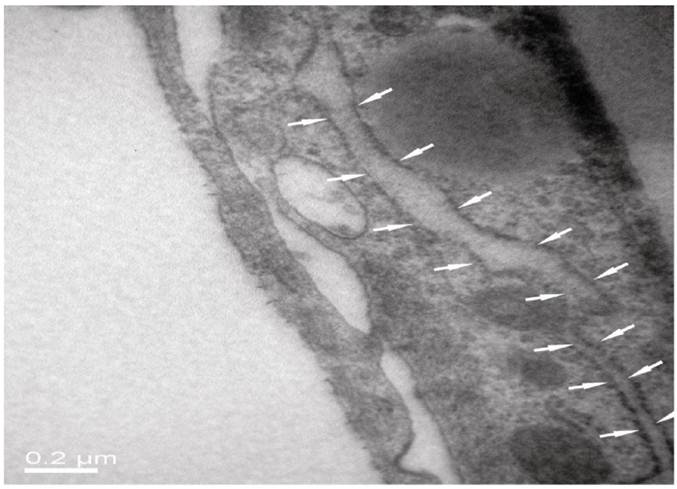

As seen from Fig. 5 of HE staining results, neurons, BMECs and astrocytes in the NVU model formed as a continuous single layer, respectively. Interestingly, numerous eosin staining exists in the micropore of the inner side of the insert membrane, which could be explained that podocytic processes of astrocytes crossed the micropore of the membrane and have a direct contact with endothelial cells. The neurons grown in the bottom of the well have longer axons and more dyed nucleus, which indicated that the cells grew in a preferable condition. The TJ was determined by TEM. As shown in Fig. 6, the presence of electron-dense material in the space between cells reflects the TJ.

Fig 6

TJ of the neighboring endothelial cells determined by TEM.